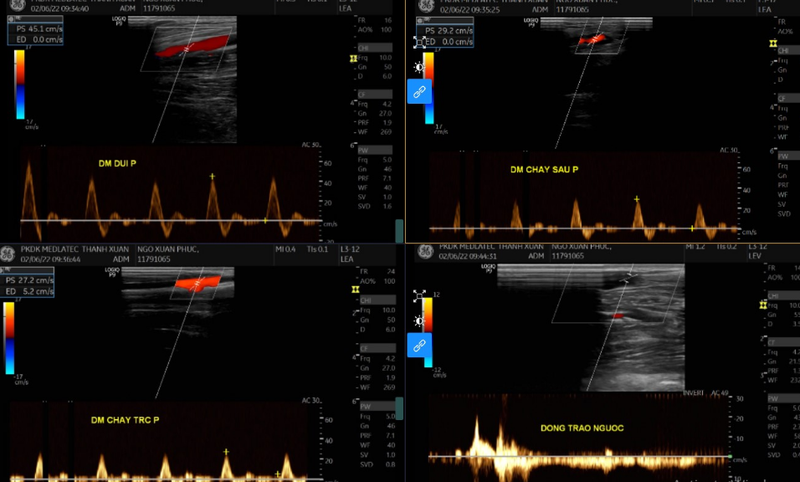

Siêu âm Duplex động mạch xác định được những thay đổi của dòng máu lưu thông trong động mạch bị viêm tắc như giảm lưu lượng máu, giảm tốc độ dòng máu, xuất hiện các cục nghẽn,...

Kỹ thuật siêu âm sẽ giúp đánh giá dòng chảy ngược trong các tĩnh mạch sâu, các tĩnh mạch nông nằm giữa các lớp cơ cẳng chân và đánh giá cả các tĩnh mạch xuyên, nối giữa tĩnh mạch nông và sâu.

Dựa vào kết quả siêu âm Duplex và một số dấu hiệu khác, nếu dòng chảy ngược ở một đoạn tĩnh mạch nào đó dài hơn thời gian bình thường, các bác sĩ sẽ có một hướng điều trị phù hợp.